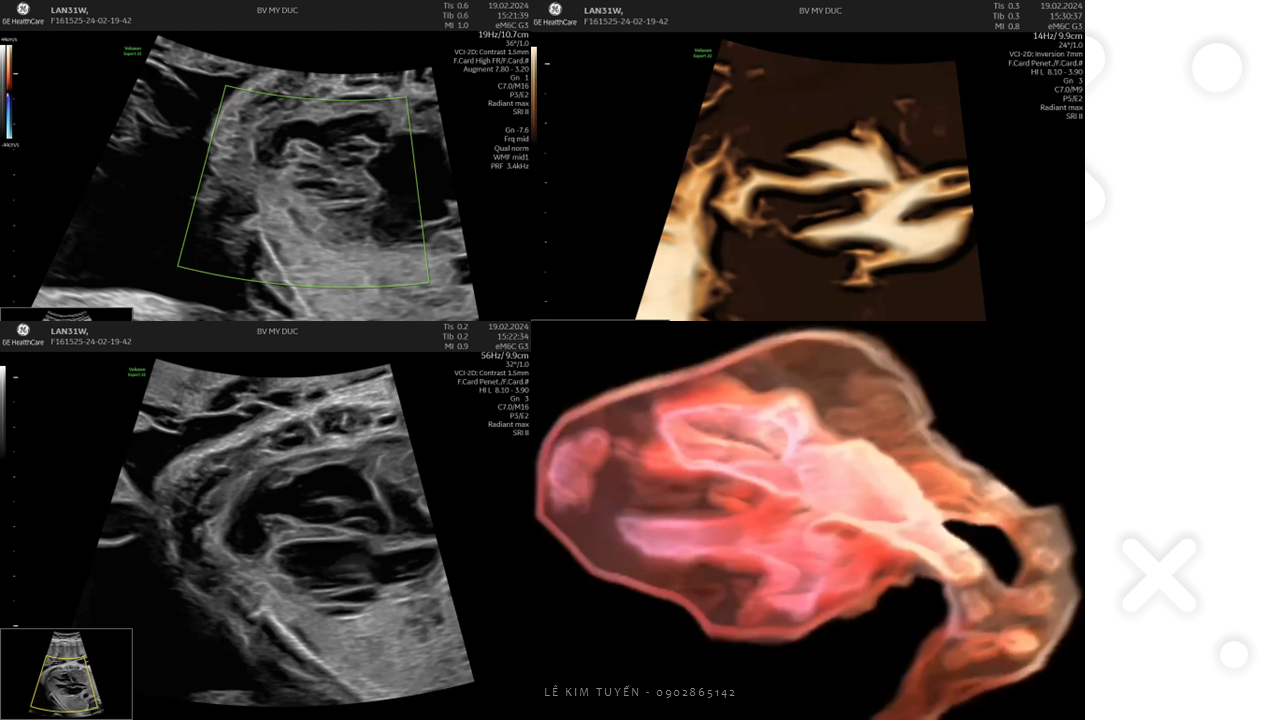

Siêu âm tim thai - Các kỹ thuật hiện đại

TS. BS. Lê Kim Tuyến